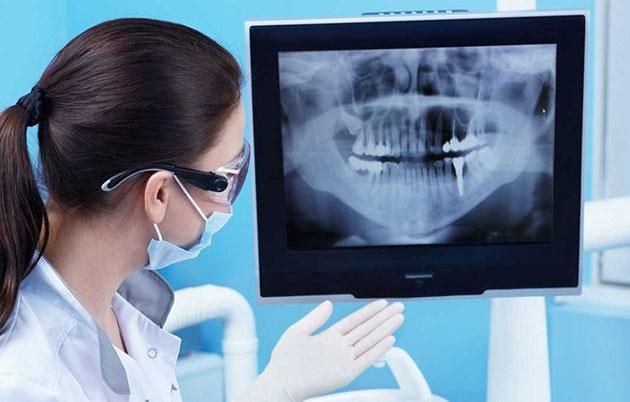

- Chụp răng: Được sử dụng để phát hiện sâu răng ở các kẽ, sâu răng tái phát, cũng như các bệnh về nướu. Phim X-Quang quanh chóp răng còn giúp xác định tình trạng tiêu xương, răng ngầm dưới nướu và hình dạng xương nâng đỡ răng. Ngoài ra, kỹ thuật này còn giúp đánh giá hình dáng chân răng và mức độ nguy hiểm của nhiễm trùng. Phim X-Quang nha khoa thường là loại nhỏ và chi phí khá hợp lý.